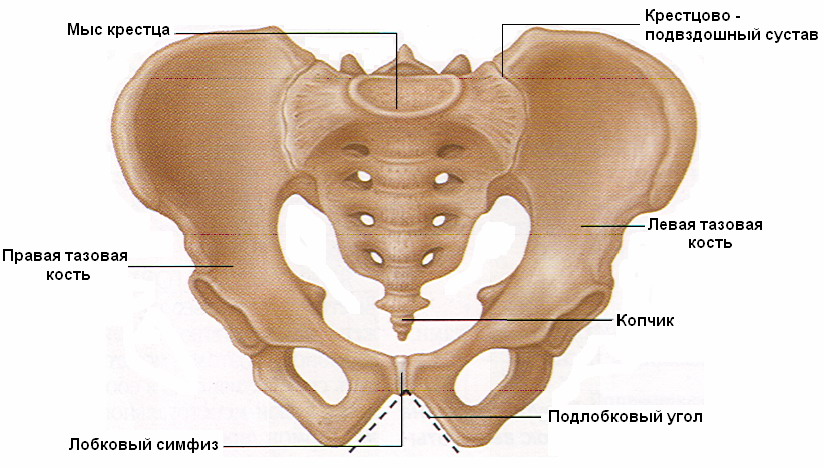

Анатомия малого таза: детальные схемы и изображения